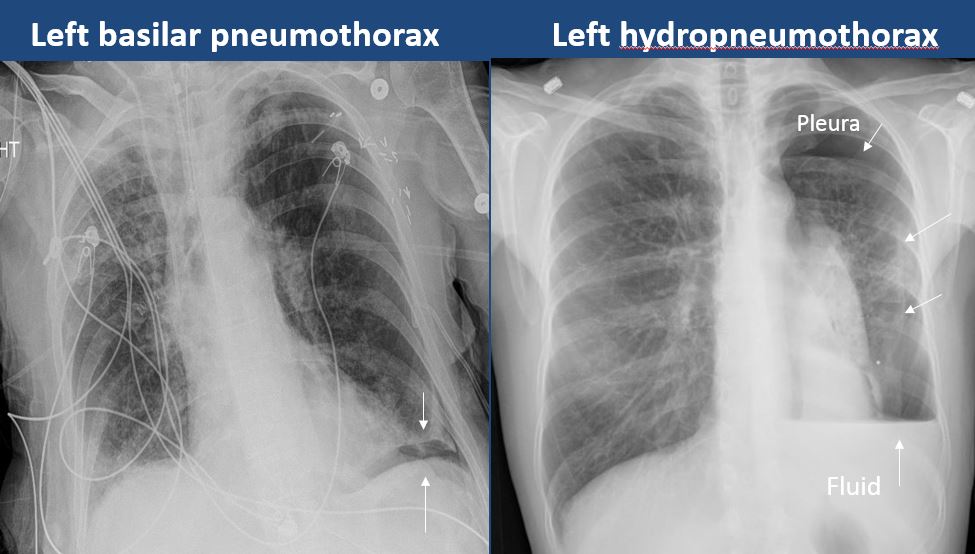

Pleura

​There is focal or diffuse abnormality of the pleura or chest wall.